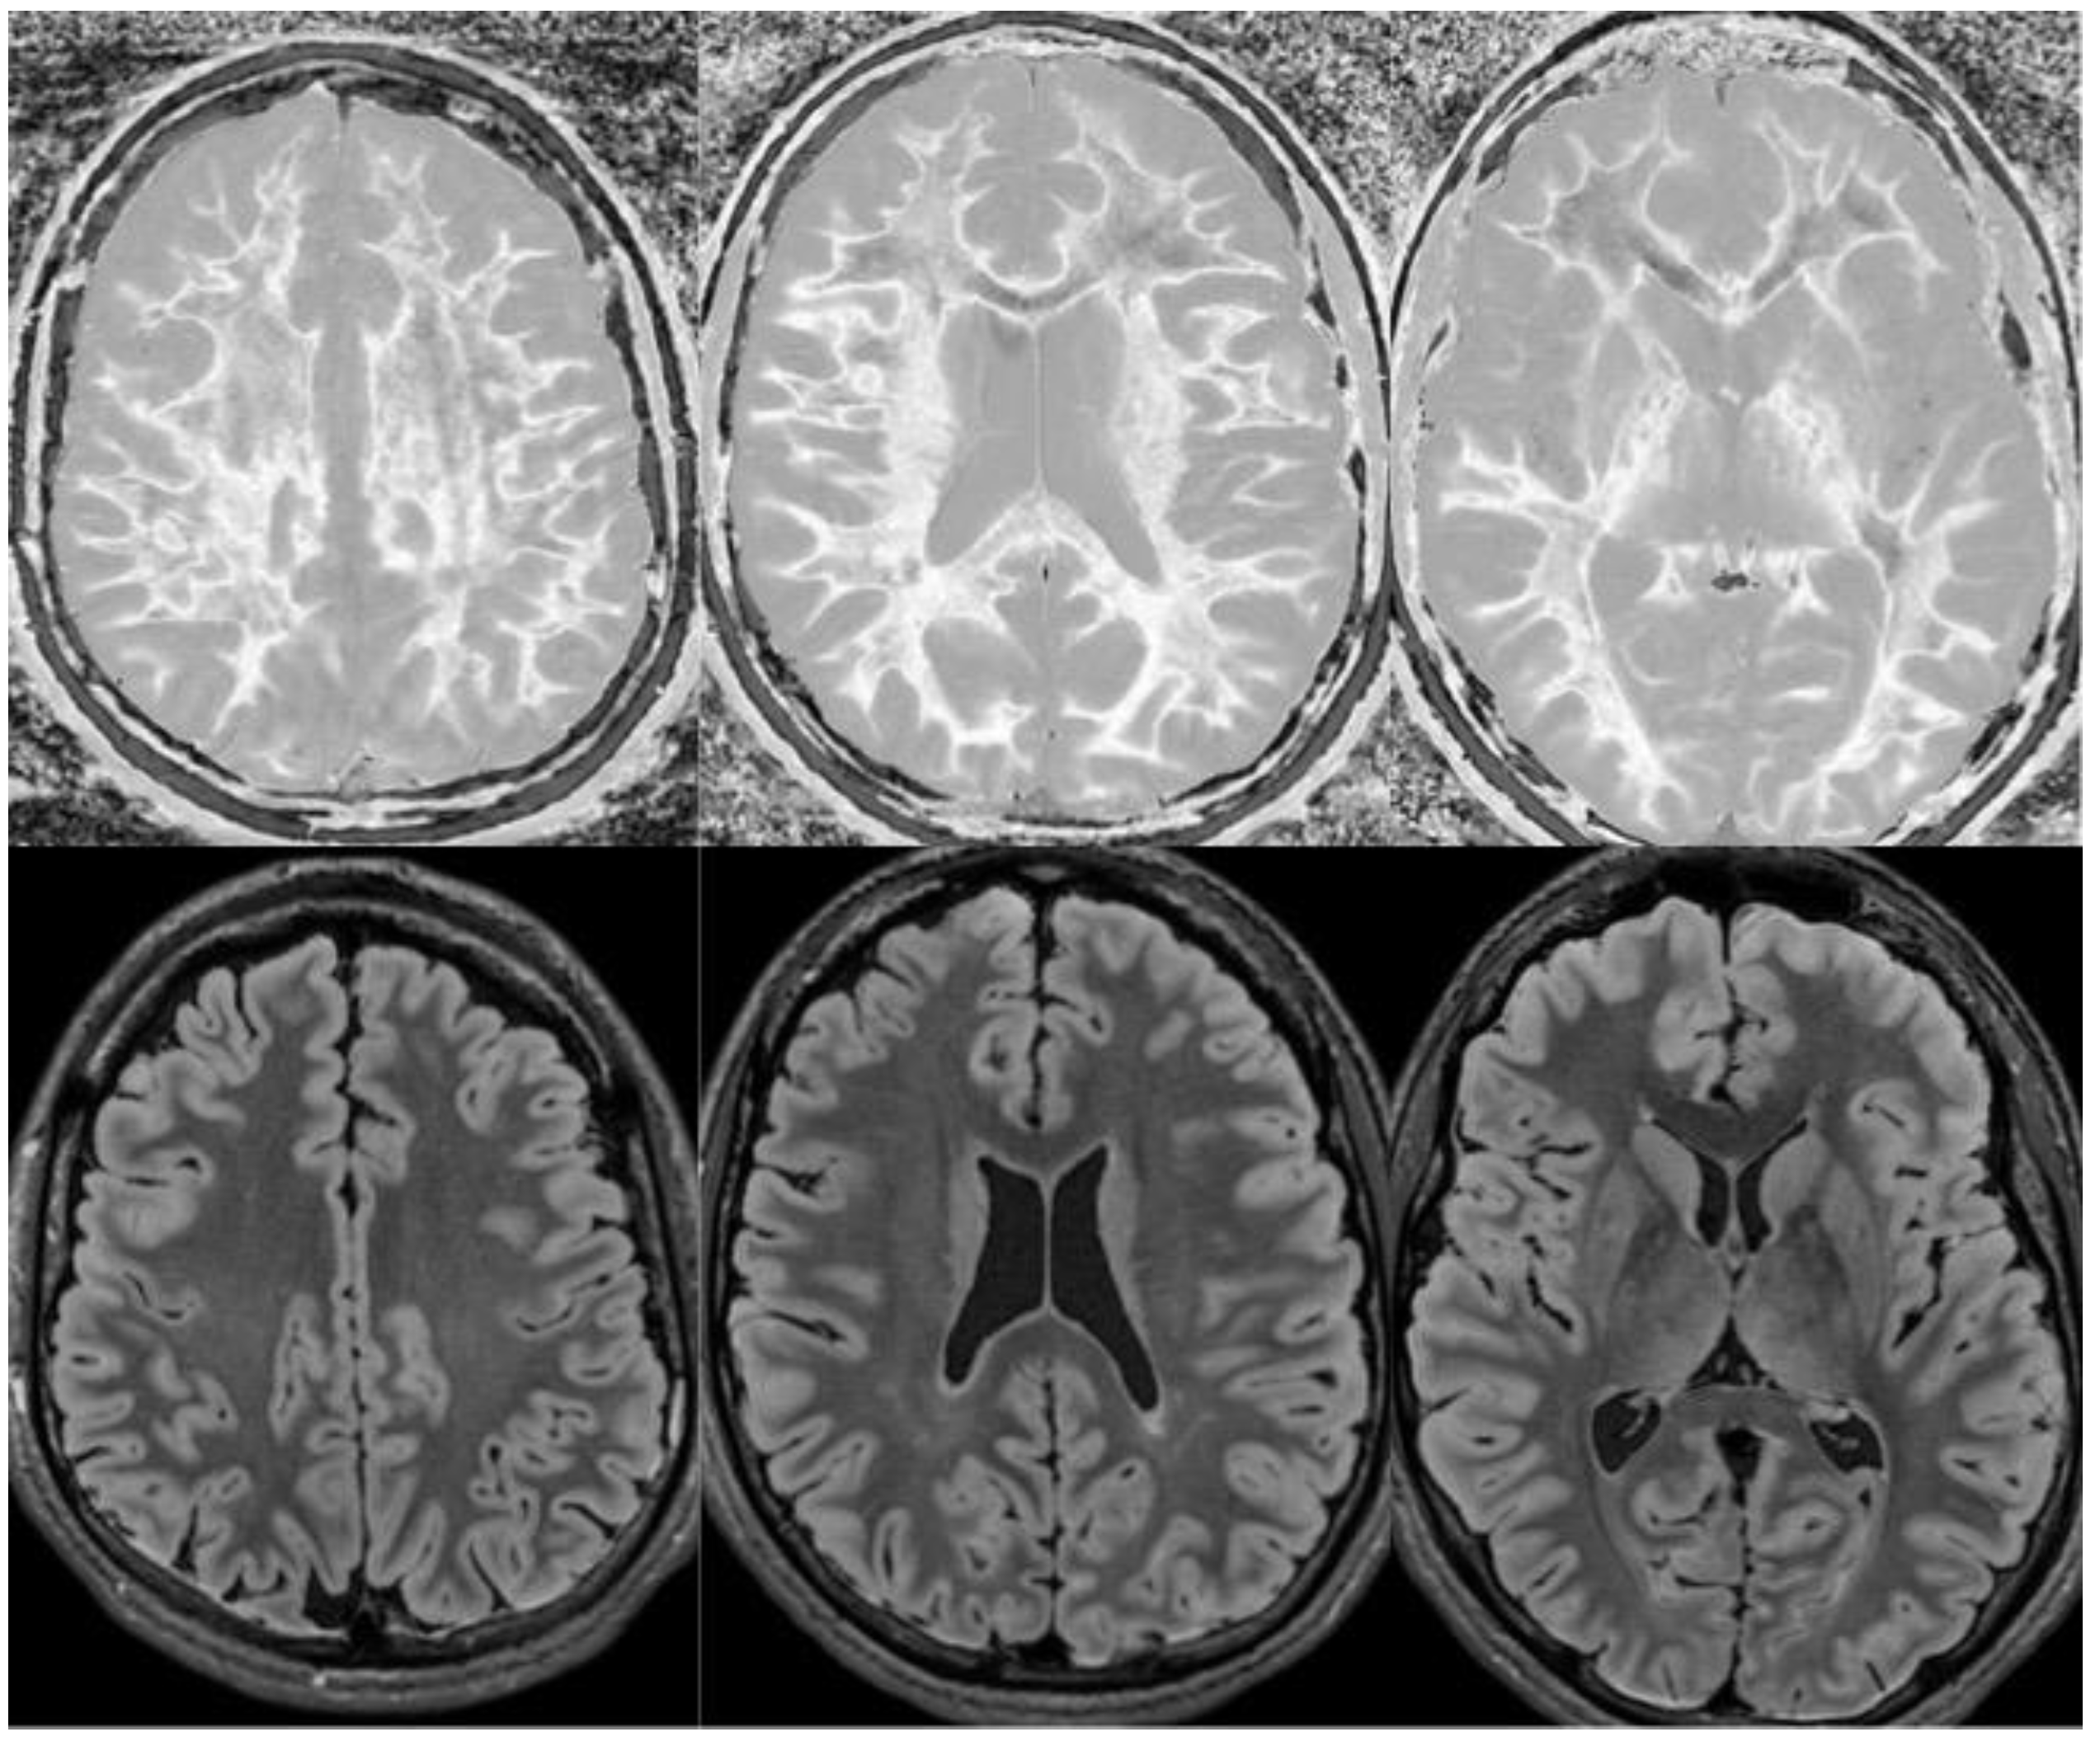

Figure 14.

Normal and abnormal divided Subtracted Inversion Recovery (dSIR) images. Narrow middle domain images in three patients at the level of the centrum semiovale. TIshort = 350 ms. TIlong = 500 ms. TE = 7 ms, TR = 5000 ms. The left image shows an example of the “white out sign”, with a diffusely increased signal throughout the white matter. The center image is an example of normal. The white matter has a mildly increased signal that is normal because TIshort = 350 ms nulls tissue with T1 values less than that of white matter. The image on the right has an intermediate appearance, probably abnormal but not a “white out”.

Figure 15.

Divided Subtracted Inversion Recovery (dSIR) in a patient with Grinker’s myelinopathy. Top row: Narrow middle domain dSIR images at the level of the centrum semiovale (left), corona radiata (middle), and basal ganglia (right) in a patient with persistent symptoms following prolonged hypoxia due to a suicide attempt. TIshort = 350 ms. TIlong = 500 ms. TE = 7 ms, TR = 5000 ms. There is a diffuse “white out”. Bottom row: T2-FLAIR images at matching levels show normal-appearing white matter. Scans were obtained 9 months following injury.

Figure 16.

Divided Subtracted Inversion Recovery (dSIR) in a patient with Grinker’s myelinopathy. Top row: Narrow middle domain dSIR images at the level of the centrum semiovale (left), corona radiata (middle), and basal ganglia (right) in a patient with persistent symptoms following prolonged hypoxia due to drug overdose. TIshort = 350 ms. TIlong = 500 ms. TE = 7 ms, TR = 5000 ms. There is widespread “white out”, with some sparing in the deep frontal lobe white matter. Bottom row: T2-FLAIR images at matching levels show normal-appearing white matter. Scans were obtained 2 years following injury.